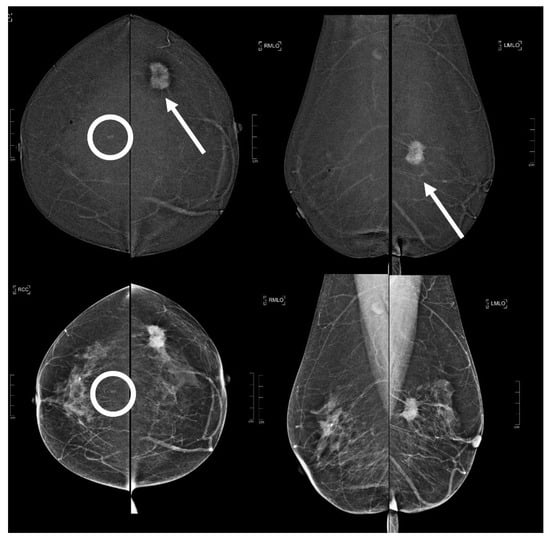

Figure 3.

A 73 year old patient. Contrast-enhanced digital mammography performed as preoperative staging for a B5 lesion in the left breast (arrows). In the early RC in the right breast, there was an enhancing asymmetry in the upper quadrants with high conspicuity only visible in MLO (circle). The EA did not have a clear correspondence in low-energy images. The patient underwent SL-US, which showed a hypoechoic mass of 6.0 mm that was subsequently subjected to CNB (core needle biopsy), which confirmed an invasive tubular carcinoma.